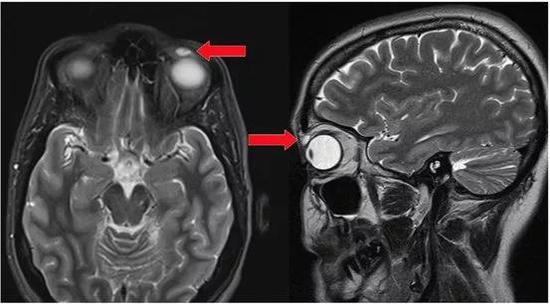

吃松鼠大脑引发罕见脑感染

纽约一名男子在吃了松鼠大脑后,患上了一种极其罕见且致命的脑部疾病。这位61岁的老人在经历思维能力下降和与现实脱节后被送往医院。他的家人说他喜欢打猎,据报道他吃了松鼠的大脑。这种奇怪的饮食习惯可能使他面临变异型克雅氏病( vCJD )的风险,这是一种由传染性蛋白朊病毒引起的致命脑部疾病。

事实上,医生对这名男子头部进行MRI扫描后发现了与vCJD患者相似的状况。医生认为这名男子可能患有vCJD,尽管尸检尚未正式确诊。据悉,只有几百例vCJD病例被报道过,其中大多数与英国在1980年代和1990年代食用受污染的牛肉有关。

该病例发生在2015年,在2018年10月传染病科学会议上首次报告。